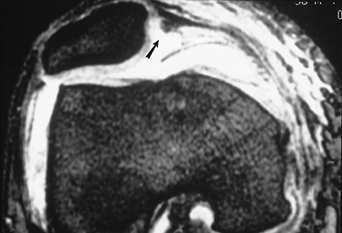

P.273

|

FIGURE 5-52 Axial gradient echo image demonstrating lateral subluxation and a tear (arrow) of the medial retinaculum.

![]() |

FIGURE 5-53 Sagittal (A) and axial (B)

T2-weighted MR images after patellar dislocation with fluid–fluid levels, retinacular tear, and shaving of the patellar articular cartilage (arrow). |